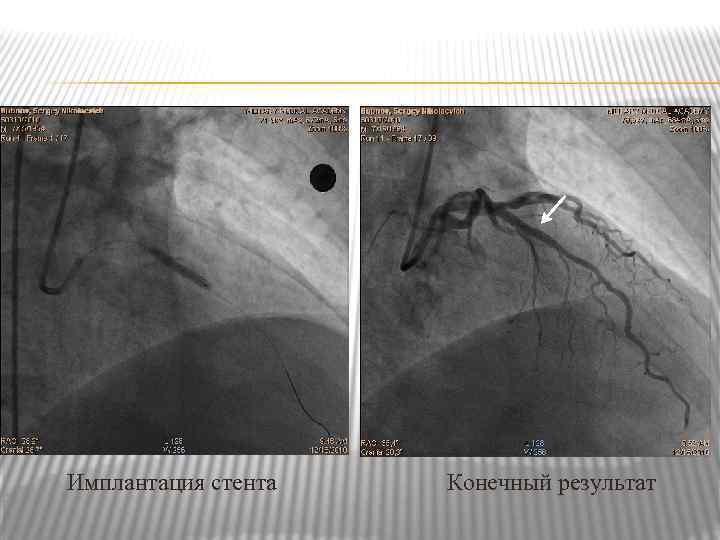

Имплантация стента Конечный результат

Имплантация стента Конечный результат